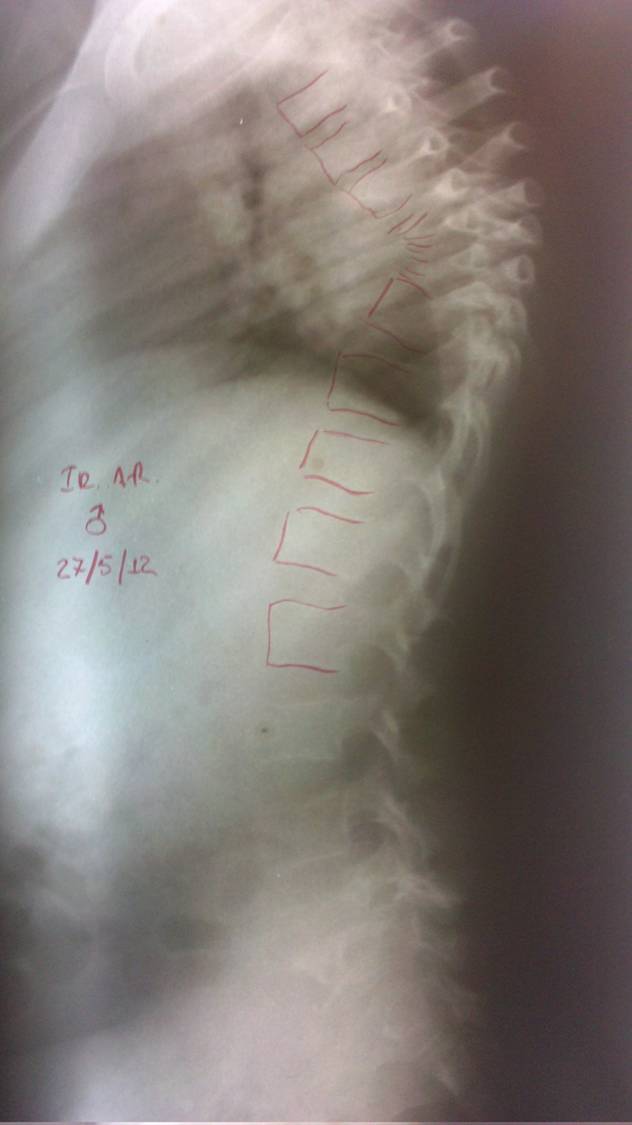

- Figura No 3a

- Figura No 3b

- Figura No 3c

- Figura No 3d

- Figura No 3e

- Figura No 3f

- Figura No 3g

- Figura No 3h

- Figura No 3i

- Figura 3 Texto